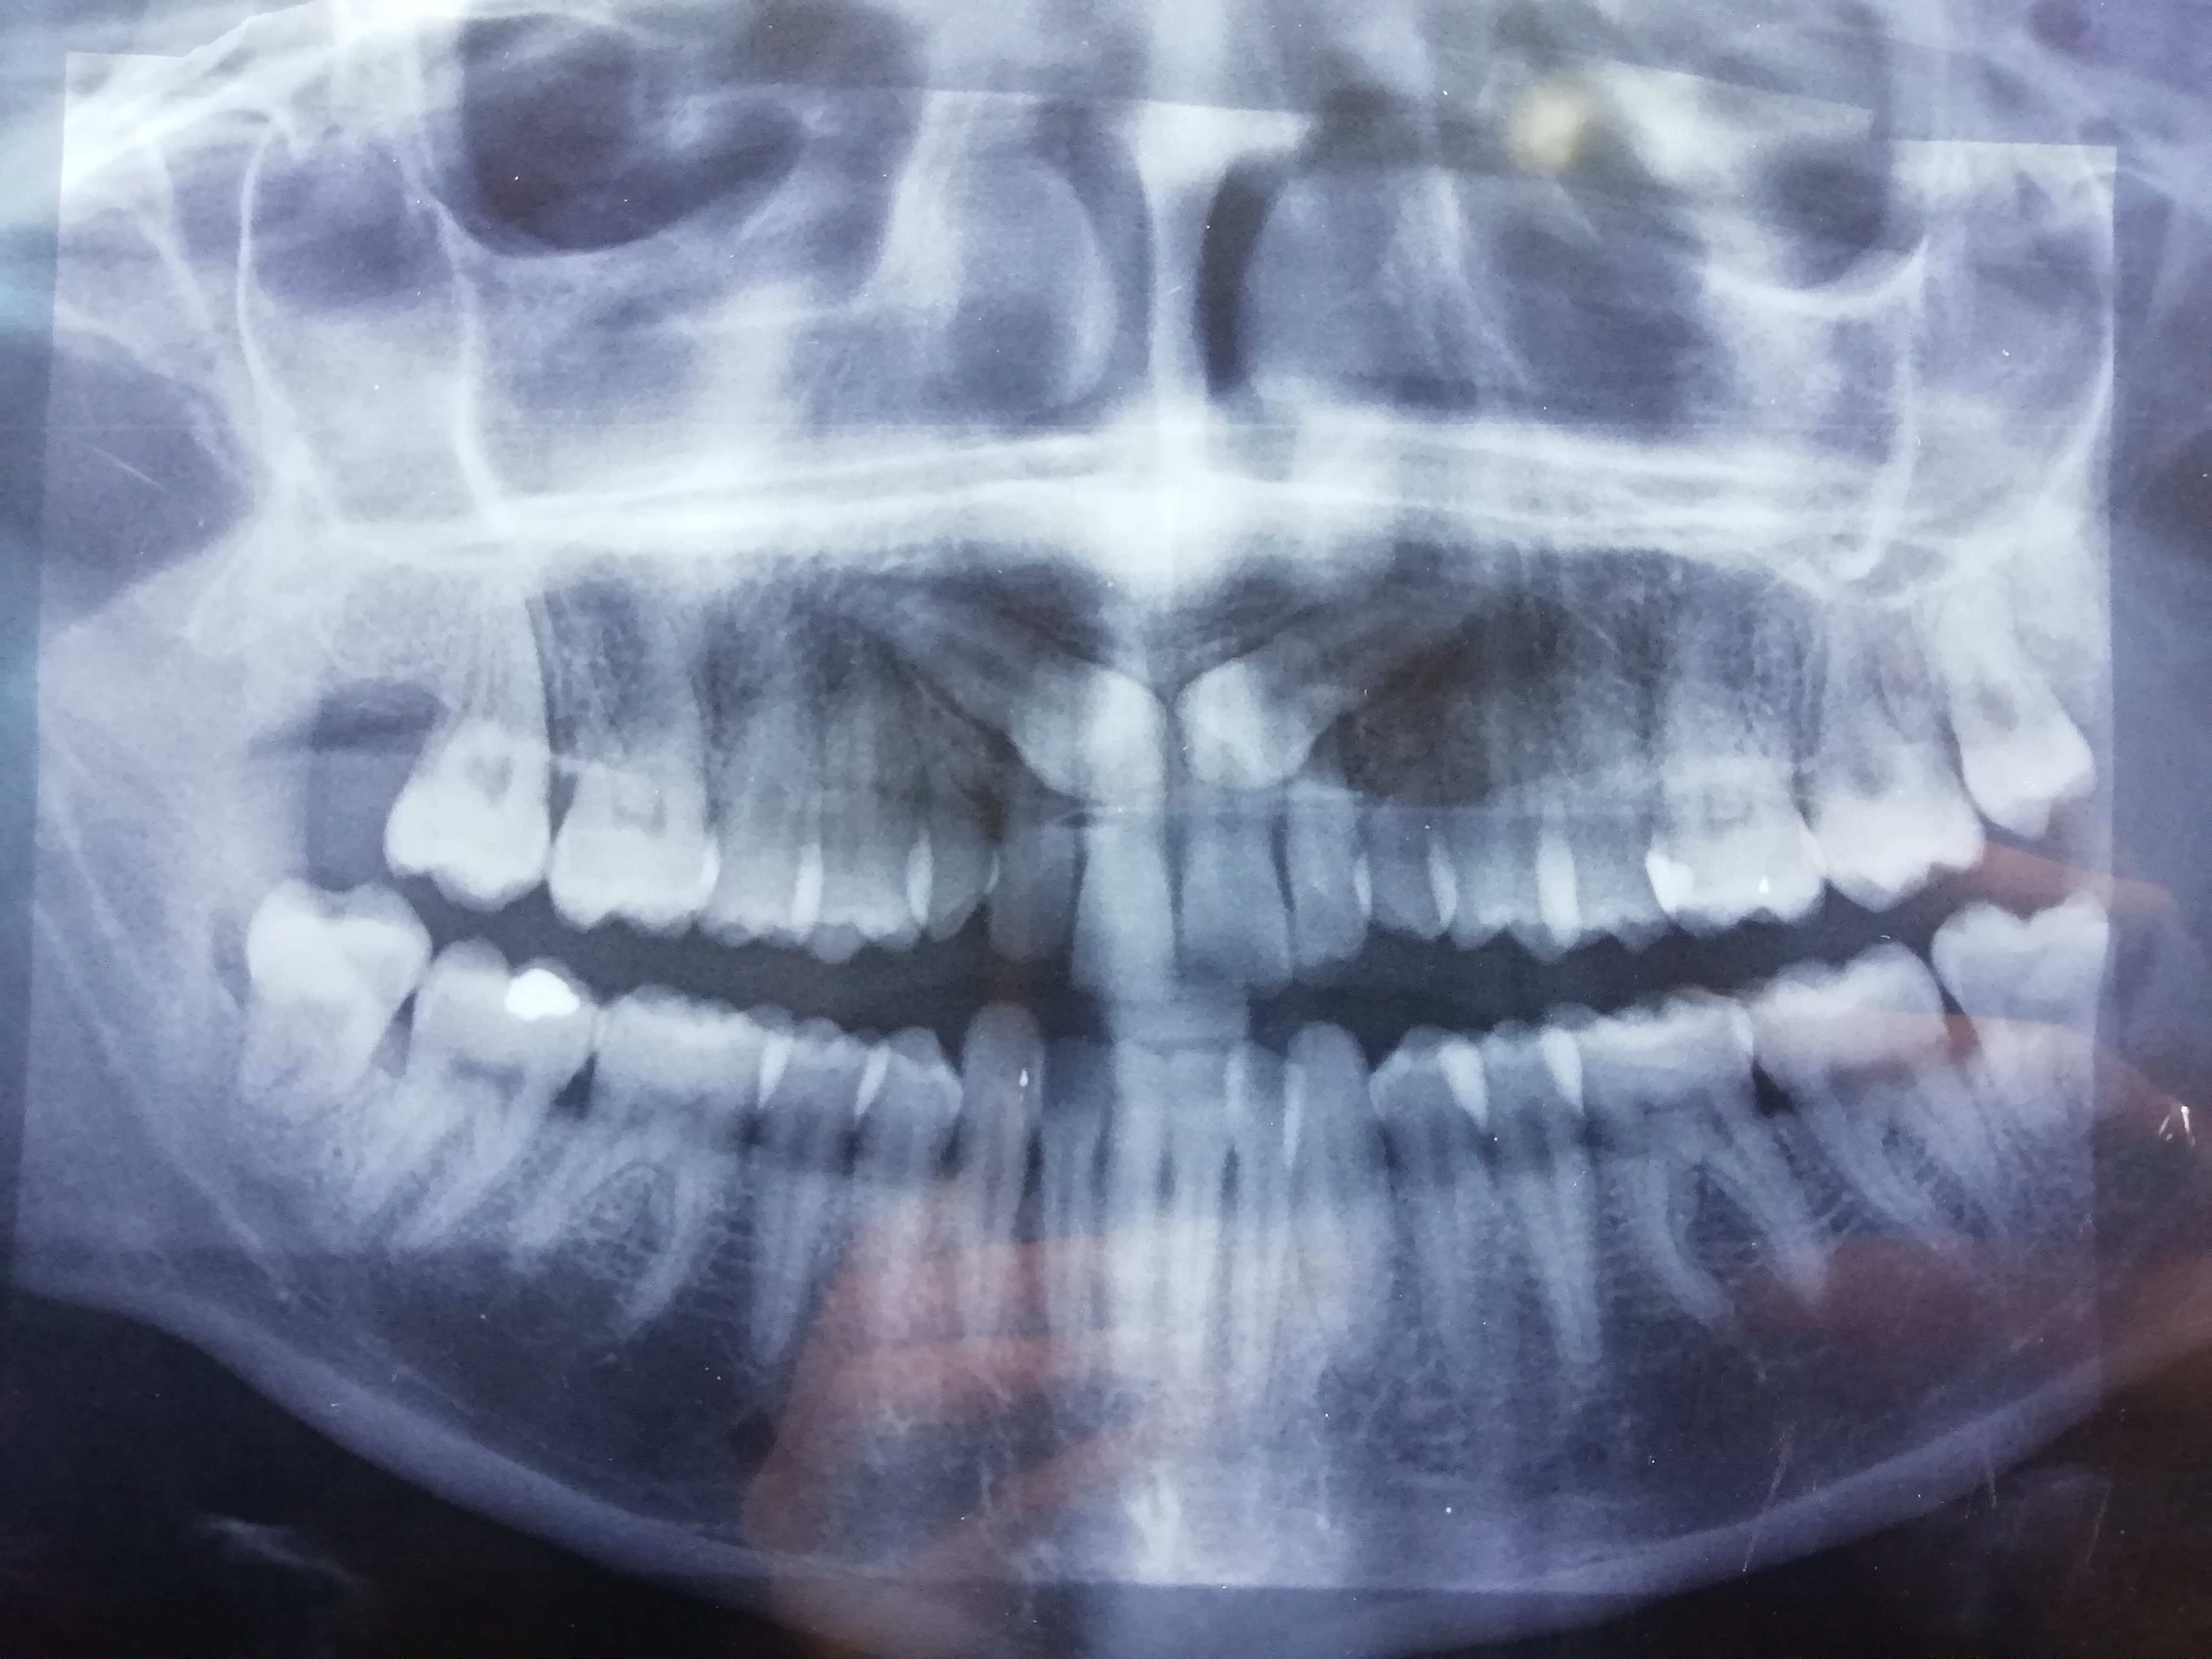

Salve, ho un problema, un paio di giorni fa mi sono accorto di avere un qualcosa che spuntava dall'ultimo dente inferiore sinistro, all'inizio ho pensato potesse essere una parte del dente del giudizio, ma non ne ho la certezza e ho paura che possa essere qualcos'altro, in questo momento non posso consultare il mio dentista

Leggi tutto